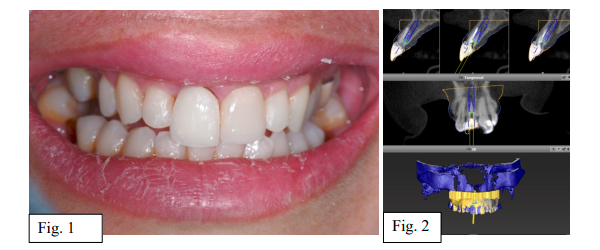

A paciente TAC, 39 anos, sexo feminino, procurou clínica privada com história de trauma bucal e posterior soltura da coroa do dente 11 (Fig. 1). Após avaliação clínica e tomográfica, foi diagnosticado fratura radicular. Dessa forma, seguiu-se com o planejamento para instalação de implante imediato com planejamento virtual e impressão de guia cirúrgica para instalação guiada com kit de Cirurgia Guiada da Implacil (Fig. 2).

Para o tratamento, foram seguidas todas as condutas cirúrgicas recomendadas na zona anterior da maxila, especialmente em pacientes com expectativa de excelência no resultado estético. Primeiramente, a exodontia com menor trauma possível (Fig. 3 e 4).